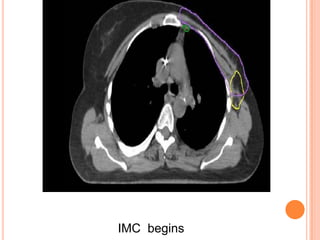

IMC begins